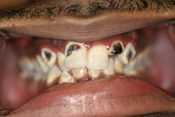

WORST TEETH Pictures from Warren Dentistry

This can happen to your teeth when proper Dental Hygiene is not practiced.

Patient 4